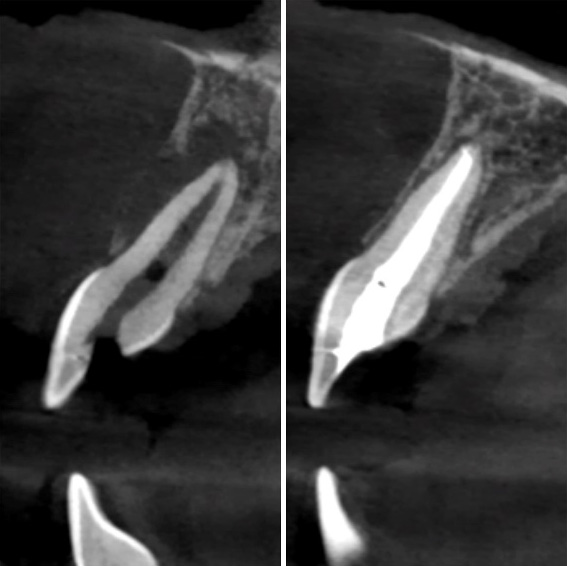

Endodontic treatment as a treatment for sinusitis of odontogenic origin

Read article